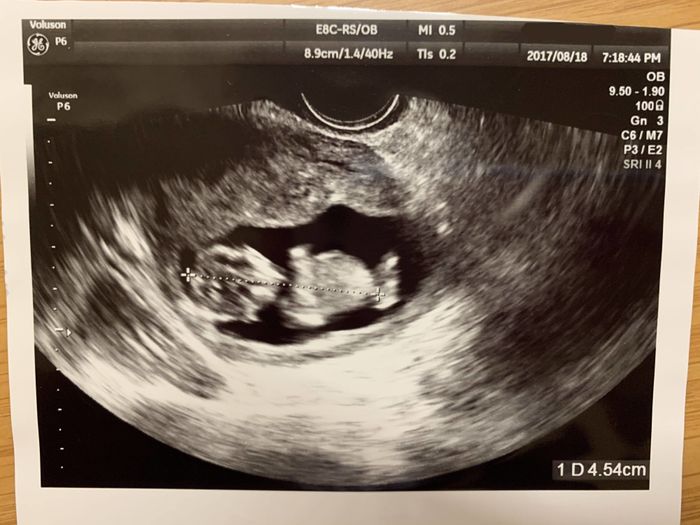

妊娠5週目 おなかの中にやってきた3人目の赤ちゃん!

上の子を二人とも不妊治療によって授かったこともあり、まさか自然に妊娠するとは思ってもいませんでした。体調不良も「夏カゼでもひいたかな?」と思っていたのですが、もしかしたらと思い妊娠検査薬で検査をしたところ、まさかの陽性! その時は、喜びよりも「なぜ?」とびっくりする気持ちの方がが強かったのを覚えています。病院のエコー検査で、ちゃんと胎嚢が確認できたとき、「ようこそ、ママのおなかへ!」と湧き上がる喜びでいっぱいでした。